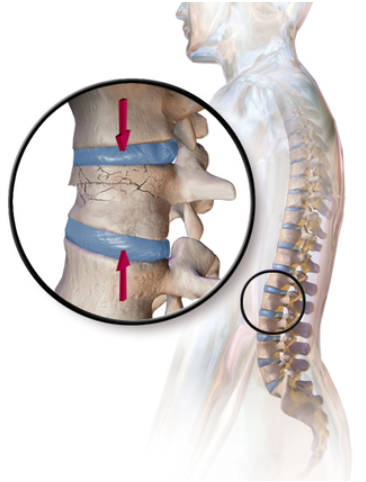

A fracture indicates that there is damage to the bones, such as a crack or a separated fragment (image 4). Traumatic injuries such as car accidents or falling on your back can cause fractures in the lumbar spine or low back region. The severity and location of the fracture in the lumbar spine will vary depending on how you were injured. For example, you are more likely to receive a burst fracture (shattering of the vertebra under compression) in a front-end accident as opposed to a rear-end accident. Depending on the severity and location of the fracture, your symptoms vary significantly. Medically, lumbar spine fractures are managed differently depending on your circumstances and decisions made with your health practitioner.

Image 4. Visual representation of a burst fracture in the lumbar vertebra. Source.